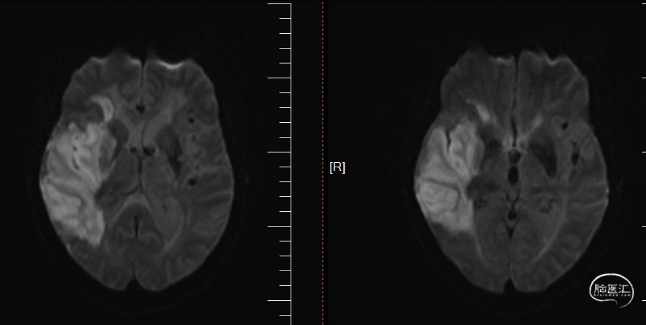

术前磁共振DWI